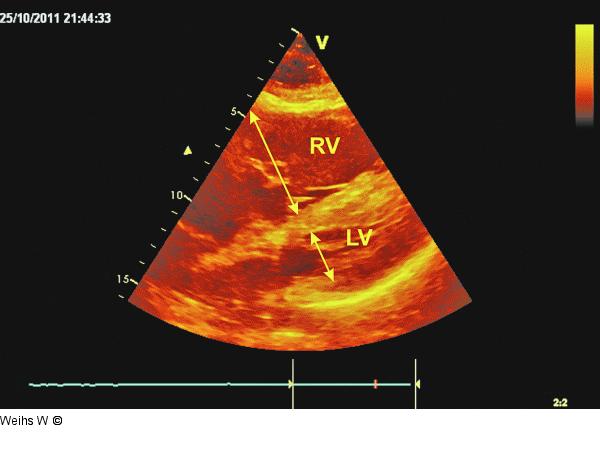

Abbildung 3: Vierkammerblick Subkostaler Vierkammerblick bei akuter Rechtsherzbelastung. Ausgeprägte Dilatation des rechten Ventrikels (vor allem im Verhältnis zum linken Ventrikel) mit reduzierter Pumpfunktion (LV: linker Ventrikel; RV: rechter Ventrikel). |

Subkostaler Vierkammerblick bei akuter Rechtsherzbelastung. Ausgeprägte Dilatation des rechten Ventrikels (vor allem im Verhältnis zum linken Ventrikel) mit reduzierter Pumpfunktion (LV: linker Ventrikel; RV: rechter Ventrikel). |